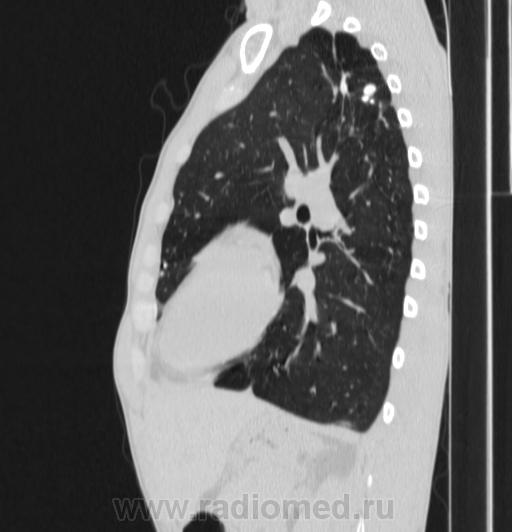

Состояние после торакопластики.

Молодой человек 30 лет, в 04 году выявлен фиброзно-кавернозный ТБ, в течение 12 месяцев лечился в стационаре, прооперирован-5реберная торакопластика справа, через 3 года переведен в 3ГДУ, в 10году снят с ДУ по излечению. Пришел провериться по ухудшению состояния. На КТ легких данных за рецидив ТБ, вроде нет. С " торакопластикой" был единственным пациентом на учете.

Состояние после правосторонней 5-реберной торакопластики по поводу ФКТ.Грубые остаточные изменения:поликистоз,буллезно-дистрофические изменения,плевропневмоцирроз правого легкого..Нет ли  мелкоочаговой диссеминации в обоих легких?Нужен Rархив.(ПТД).

Нет, это кальцинаты и более плотные уже. Архив только пленочный, 8 лет назад "цифры" не было. Можно и пленку перефотать...

Редко встречалось, а на КТ вижу впервые, спасибо за случай! На показанных изображениях отсевов не увидела.